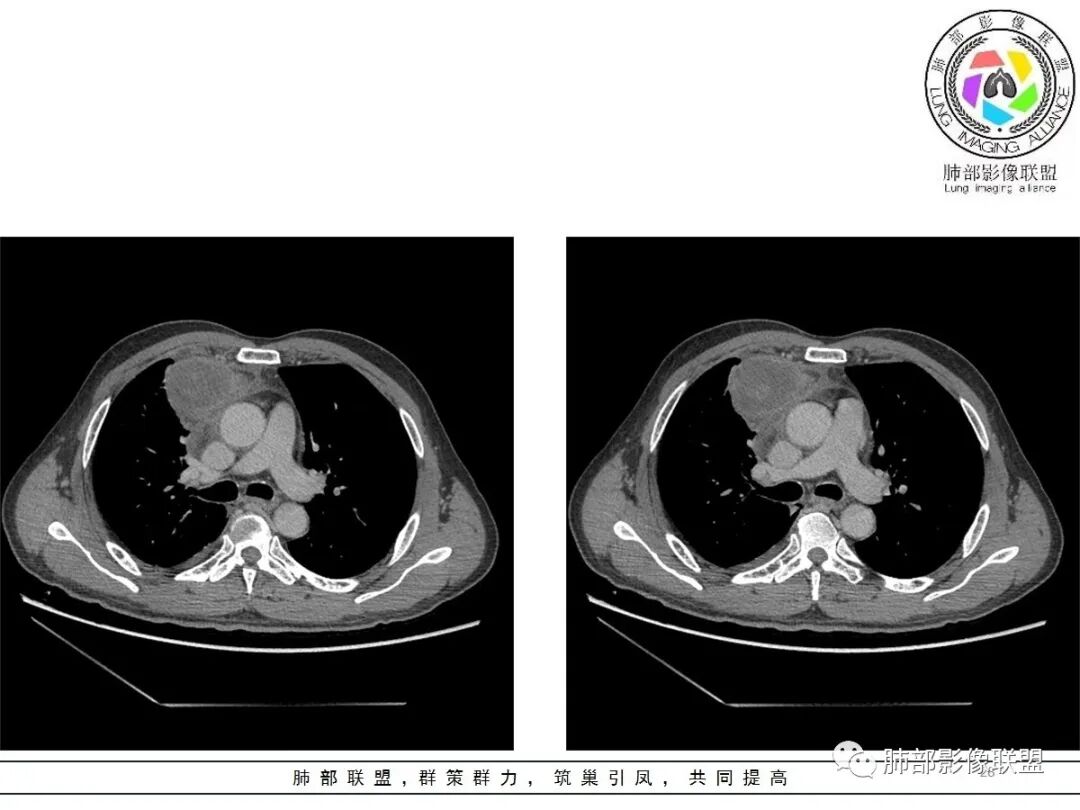

小赵:这个是3月15日的视频

小赵:第二个是3月19日的视频

2.胸膜掀起,右侧内乳动脉略增粗,定位右前上纵隔内占位。

3.右上纵隔囊实性占位,边界清楚。中央见点状脂肪密度影,边缘见一点状钙化影,增强不均匀环形强化。

4.四天内病灶变化快,块影增大且不规则,包膜似不完整,边界不清,上份可见浸润或渗出,与周围心脏大血管及心包等间隙不清。胸水增多。

5.未见明显淋巴结增大

第一次的检查符合胸腺瘤影像学改变,短期内的形态学改变及突然出现的边界模糊或浸润等,符合出血或炎症。